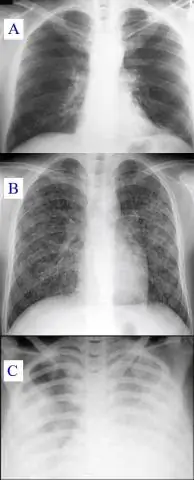

Кроме того, est-ce qu'une influenzaire est grave? Une легочная инфекция есть неизлечимая болезнь могила qui touche n'importe quelle partie des пумы (трахея, бронха, мочка легочный врач). Sous ce terme se Trouvent Plusieurs Maladies, de la plus courante (бронхит, пневмония, пневмопатия) à la plus sérieuse (бронхо-пневмония, abcès du пумон, туберкулезный).